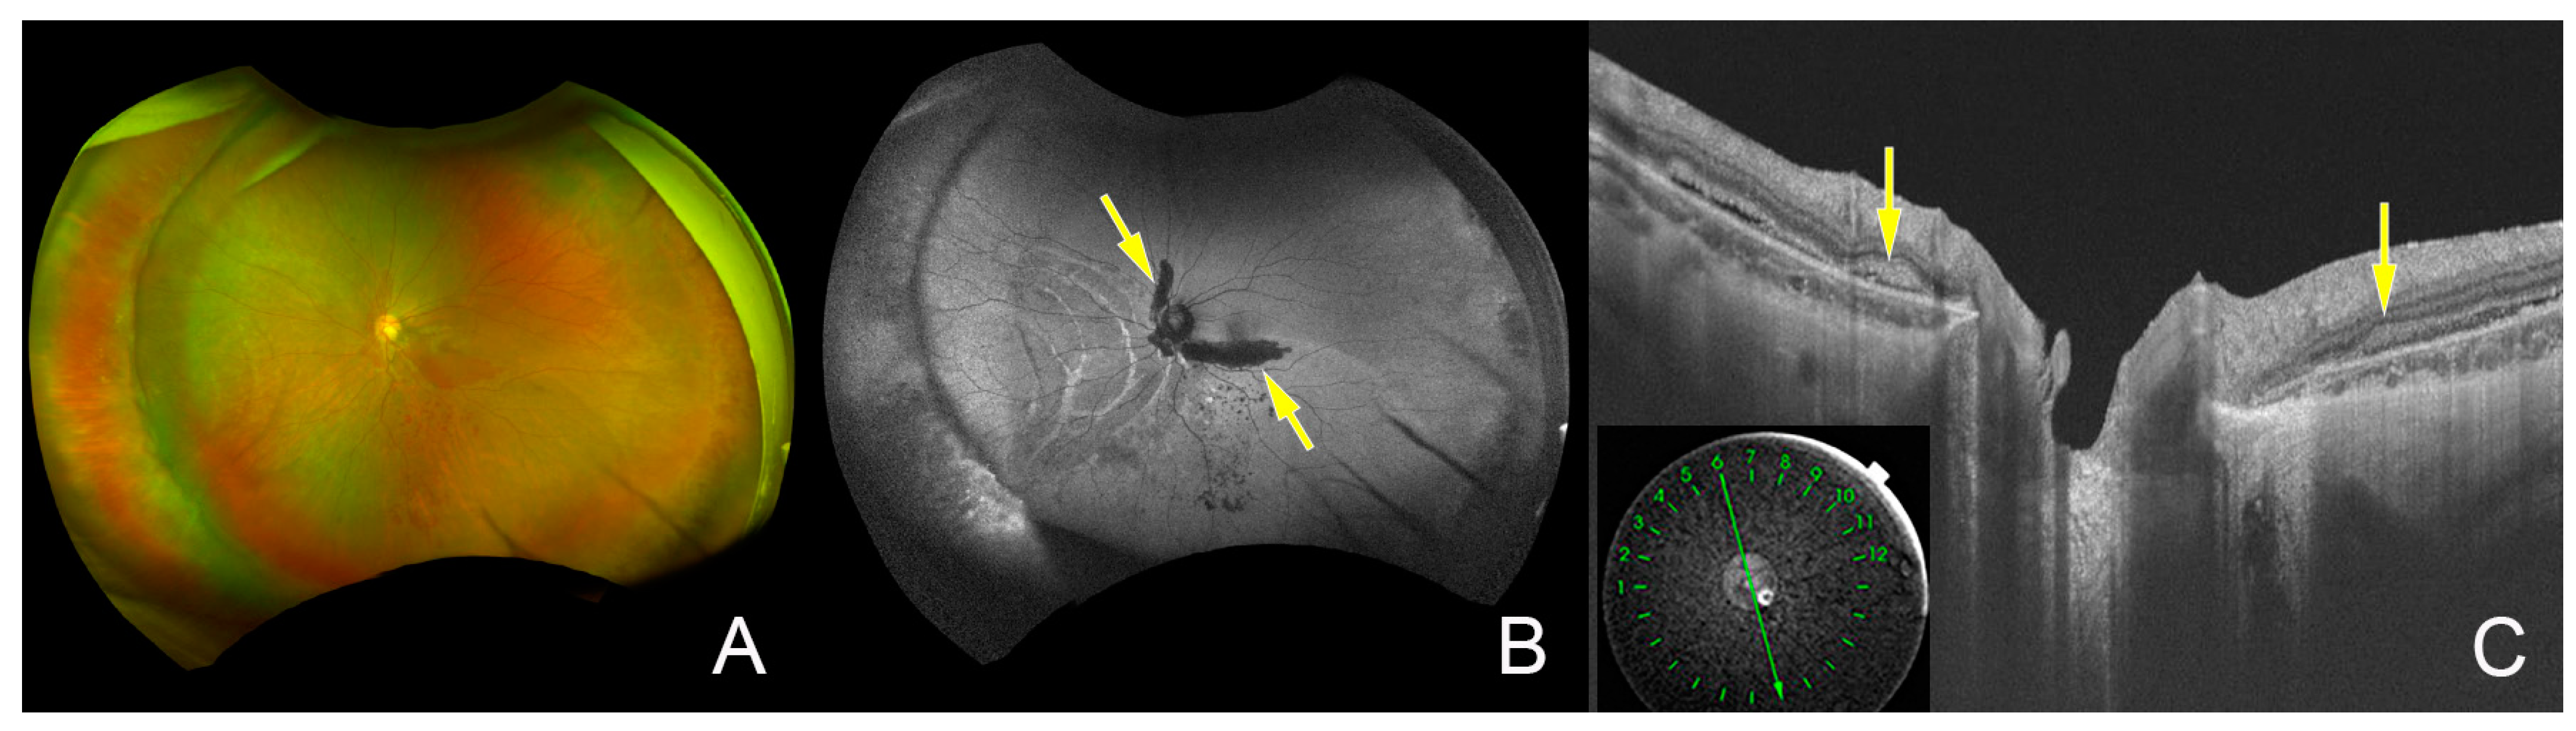

2. Case Report